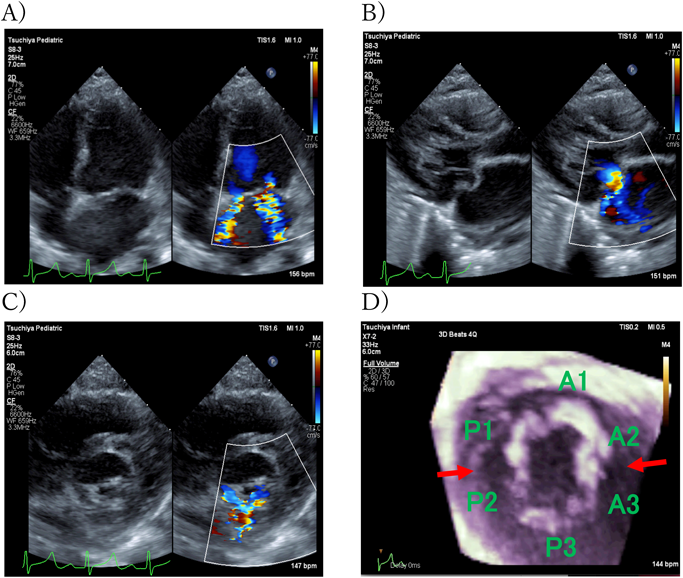

発熱前に弁破壊による急性僧帽弁閉鎖不全で発症した感染性心内膜炎の乳児例A Case of Infantile Infective Endocarditis Presenting Acute Mitral Regurgitation due to Valvular Destruction without Fever